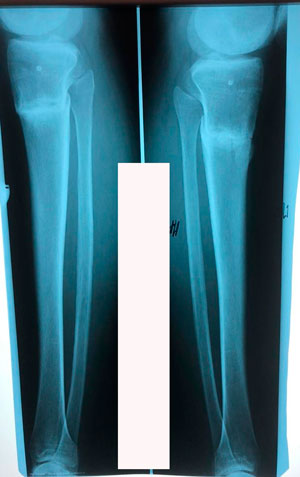

Перед крутками

IMG_6828-31-10-19-07-57.JPG